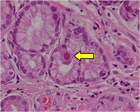

1. 患者背景、臨床症状からCMV腸炎を疑う場合は、組織採取が行える内視鏡検査が勧められる(推奨度1)

1. CMV腸炎診断のための内視鏡検査は、深部大腸まで観察し、潰瘍だけでなく、びらん、発赤、などの粘膜変化からも生検することが勧められる(推奨度2)